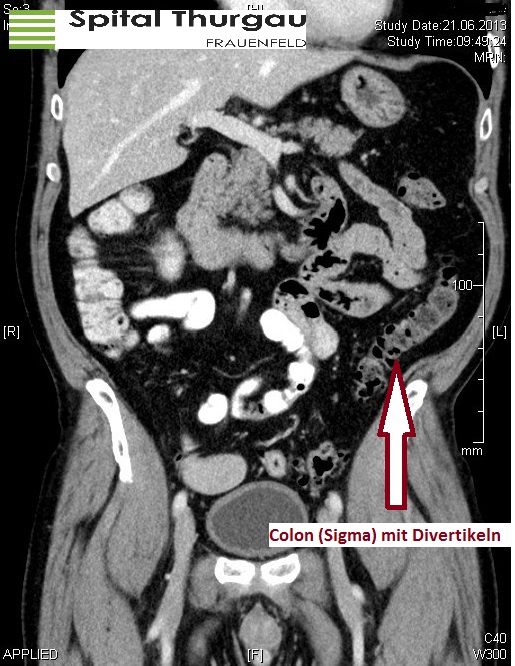

Ein Divertikel bildet sich aus Darmschleimhaut, welche sich durch kleine Lücken der muskulären Darmwand hindurchdrückt. Als Ursache geht man von einer Drucksteigerung im Übergang zwischen Sigma und Rektum (Hochdruckzone des Dickdarms) aus. Diese Divertikel nehmen im Alter zu, bei etwa 60-70% der 70-jährigen Patientinnen und Patienten ist eine sogenannte Divertikulose in der Darmspiegelung zu erkennen. Entzündet sich eines dieser Divertikel, spricht man von einer Divertikulitis. Meist kommt es zu Schmerzen im linken Unterbauch, teilweise begleitet mit Obstipation und Fieber.

Die Diagnostik beginnt auch hier mit der Anamnese und der klinischen Untersuchung. Der Bauchraum wird abgetastet, oft findet sich zum Druckschmerz eine tastbare Walze im linken Unterbauch. Die weitere Diagnostik der Wahl ist anschliessend eine Computertomographie. Hier können nicht nur Entzündungen, sondern auch kleinere Abszesse erkannt werden. Nachdem alle Befunde und die Blutwerte vorliegen, kann entschieden werden, welche Therapie möglich ist.